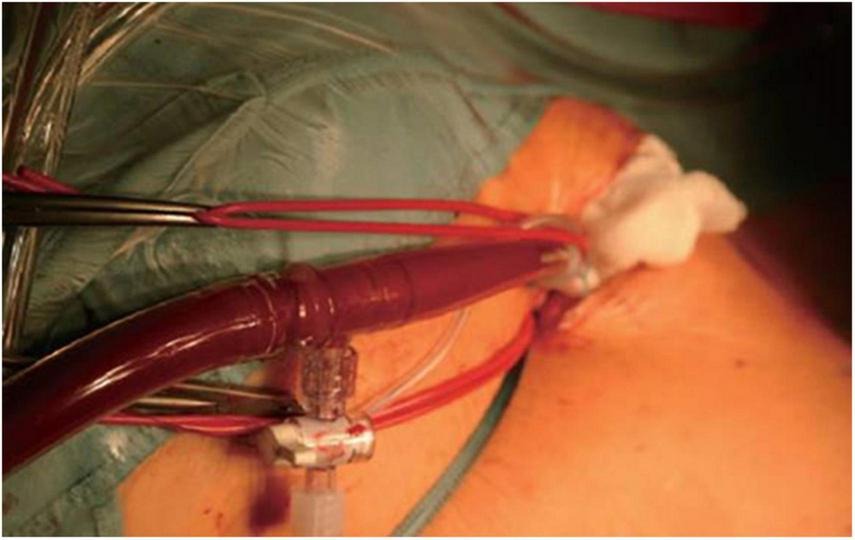

FIGURE 3

Intraoperative situs of antegrade arterial perfusion via axillaris artery in minimally-invasive mitral valve surgery.